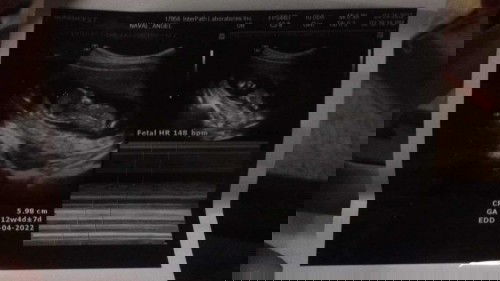

Hello good evening, ask ko lang po sainyo kung yung nakalagay po sa ultrasound nyo kung ilang weeks pregnant exact po sa date ng huli nyong regla? Sakin po kasi dec 9 last mens ko spotting na brown nag search po ako nakalagay Early sign of pregnancy. Tapos nung ultrasound ko na 12 weeks lang pala pero pag count base sa huling mens 15 weeks na. Ano po kaya tama? 15 or 12? 2 times na po ako nag ultrasound 12weeks nakalagay. Irregular po mens ko... kung 12 weeks po ako ngayun dec 30 po ako nabuntis???? Sana po ma help nyo ako mga mommies 🥰🥰🥰